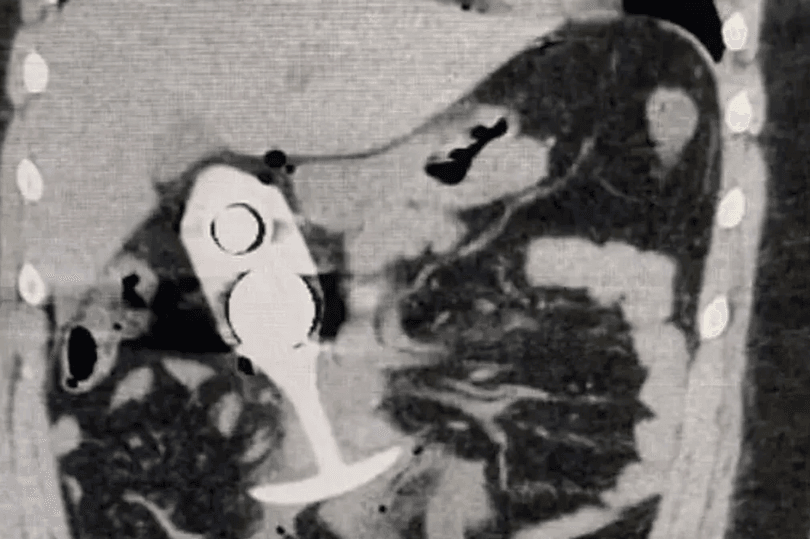

Saúde Paula Aguiar brinquedos eróticos, dicas de uso, educadora sexual, plug anal, prazer seguro, saúde íntima, segurança 0 Comentários Uso de Plug Anal Leva Paciente ao Hospital